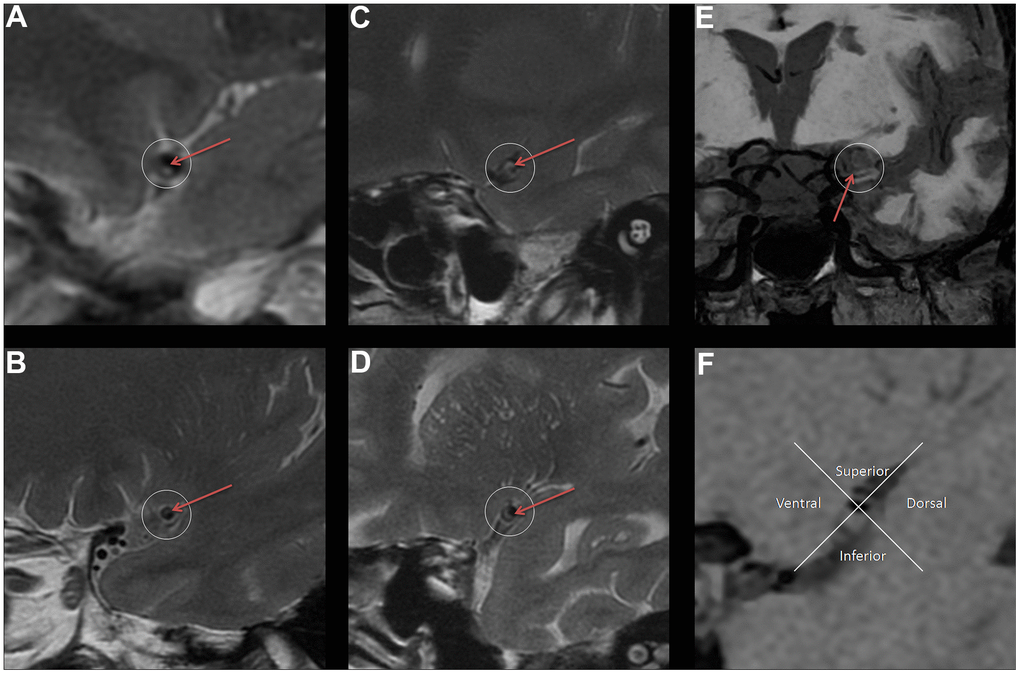

Stenosis rate (%) = [1-(stenosis lumen diameter/normal lumen diameter)] × 100%, stenosis lumen diameter is the lumen diameter at the most severe stenosis of the diseased vessel [24]. NWI = (vessel area - lumen area)/vessel area × 100%, the lumen area and vessel area at the narrowest vessel are usually measured to calculate the NWI [25]. The Remodeling ratio (RR) is the ratio of the diseased vascular area to the normal vascular area [25]. Eccentricity index = (maximum vessel wall thickness - minimum vessel wall thickness) / maximum vessel wall thickness; if the eccentricity index is ≥ 0.5, the vessel is defined as an eccentric thickening; otherwise, it is centripetal thickening [25]. Plaque location is defined as the distribution of plaques with eccentric wall thickening across the vessel and can be divided into four segments (ventral, dorsal, superior, and inferior) [26]. Plaque surface and plaque fibrous cap characteristics: according to the imaging characteristics of VWMRI images, the evaluation is usually divided into whether the plaque surface is smooth and whether the fiber cap thickness is uniform [27]. Finally, plaque characterization is also required to determine whether the plaque involves the opening of the lenticulostriate arteries on cross-sectional images (Figure 2).

Figure 2. The legend introduction of VWMRI plaque characteristics. (A) Plaque surface is irregular (red arrow). (B) Plaque surface is smooth (red arrow). (C) Uneven thickness of fibrous cap (red arrow). (D) Uniform thickness of fibrous cap (red arrow). (E) Plaque involves the opening of the lenticulostriate arteries (red arrow). (F) Distribution of plaque (The plaque is mainly located in the inferior).